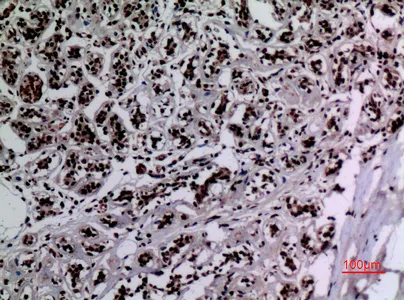

CD68 Rabbit Polyclonal Antibody

Cat: APRab08436

Size1:50μl Price1:$118

Size2:100μl Price2:$220

Size3:500μl Price3:$980

Size2:100μl Price2:$220

Size3:500μl Price3:$980